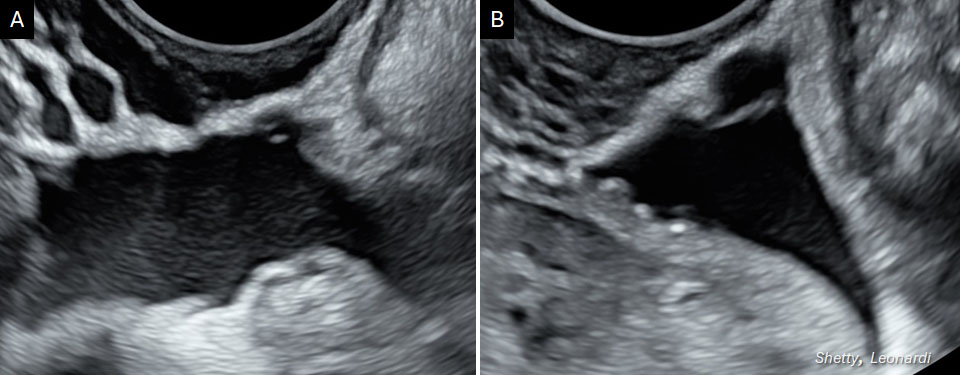

Diagnosing SE using ultrasound has been challenging due to its non-infiltrative (i.e. shallow) nature.48,64 However, a novel technique called "saline-infusion sonoPODography (SPG)" has been piloted with promising results (in those without DE, OE or POD obliteration, SE could be diagnosed with an accuracy of 80.0%, sensitivity of 77.7%, specificity of 100%, positive predictive value of 100% and negative predictive value of 33.3%).65 This technique can be combined with hysterosalpingography in the infertility clinic to assess for uterine cavity abnormalities and tubal patency. In the above pilot study, a median of 60 ml of saline was infused into the POD through patent tubes but this amount should be validated in an outpatient setting.65 This provides an acoustic window enhancing contrast in the POD peritoneum improving visualization of superficial irregularities (i.e. SE) (Figure 8) and superior RVS border (not possible without SPG) (Video 4).

.jpg?1645163)

8

Transvaginal ultrasound images showing different appearances of superficial endometriosis. (A) Cystic lesion along the peritoneal surface. (B) Hyperechoic foci and filmy adhesion forming a peritoneal pocket.